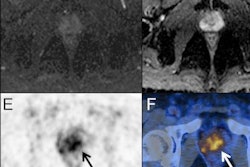

PET maximum intensity projections (MIP) of example cases in a test set with high (left), intermediate (middle), and low (right) agreement between manual expert annotation and the automated convolutional neural network (CNN)-based annotation of sites suspicious for cancer (overlayed in yellow wherever visible in the PET MIP). The number of annotated findings and miTNM nodal and metastatic stage are reported. Image courtesy of Nicolo Capobianco, PhD.The dataset included 173 prostate cancer images of patients who underwent PET/CT using F-18 DCFPyL radiotracer (Pylarify) and 193 patients who underwent PET/CT using gallium-68 (Ga-68) PSMA radiotracer. Both PET tracers are approved in the U.S. In training, the group ultimately pooled data for both tracers, Capobianco noted.

The AI model matched the expert's assessment of local and nodal cancer in 65% of cases that used F-18 DCFPyL and 79% of cases for Ga-68 PSMA-11; for metastatic lesions, the AI model matched the expert's assessment in 73% of cases that used F-18 DCFPyL and 75% cases that used Ga-68 PSMA-11, according to the findings.

"Deep-learning methods can identify regions suspicious for cancer and determine the miTNM nodal and metastatic stage in F-18 DCFPyL and Ga-68 PSMA-11 PET/CT images with moderate to good agreement with an expert physician," he said.